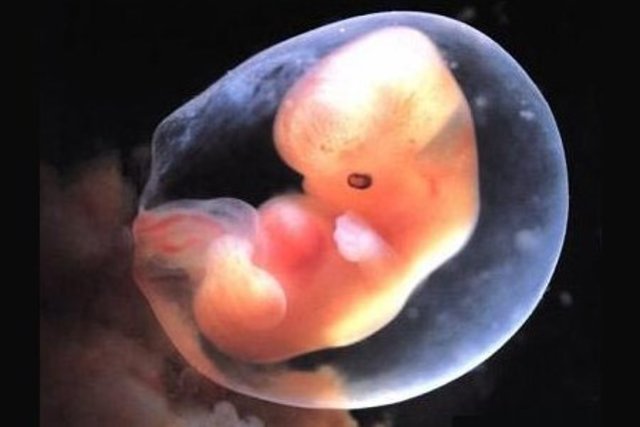

• ETAPA EMBRIONARIA.

El embrión desarrolla órganos y su cuerpo toma un molde pero es sensible a agentes que podrían darle malformaciones.

Es de la cuarta semana hasta la octava.

• 6ª Semana ETAPA EMBRIONARIA

6ª Semana ETAPA EMBRIONARIA

La cabeza crece desproporcionadamente, y los párpados se forman.